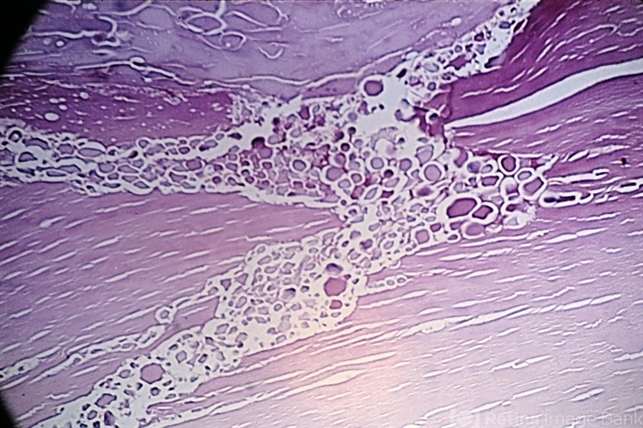

- senile cataract, lens cortex

- Morgagnian droplets in a senile cataract of the lens cortex (x40). (Scheie Eye Institute, No. 4076.)